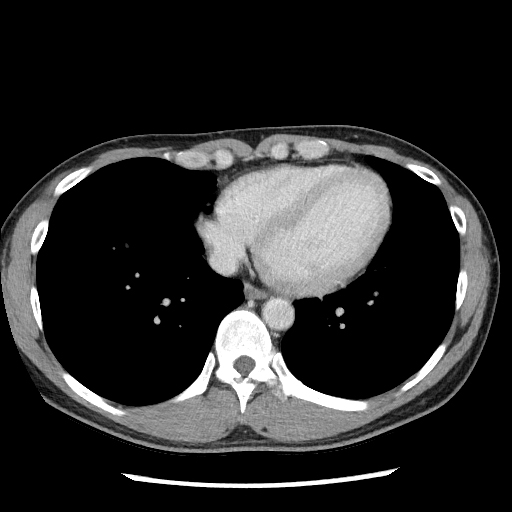

ただし,造影CTの方が単純CTよりも優れているというわけではありません.特に糞石を同定するときは,造影CTのみでは同定しにくい場合があり,単純CTでの評価が重要となってきます(図1).

A)単純CTで虫垂は17 mmと腫大し,虫垂内腔に25×12 mmの石灰化が確認できるため,糞石()を伴う虫垂炎と考えられる.

B)造影CTだと血管や腸管壁が造影され白く見えるため,糞石()が相対的に曖昧になってしまう.

よって画像から多くの情報を得るためには,特に禁忌がなければ単純+造影CTが推奨されます.